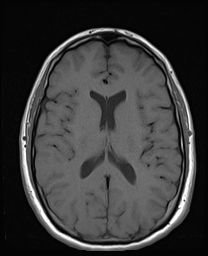

Magnetic Resonance Imaging

(MRI)

- Uses a magnetic field and pulses of radio wave energy to make pictures

- Used to detect tumors, bleeding, injury, blood vessel disease, or infection

- The best tool to detect a stroke

- Most expensive imaging study

- Must remove all metal prior to exam